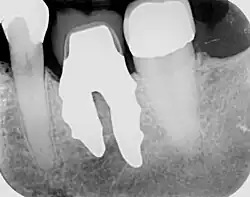

RAIs are custom made to perfectly fit the tooth socket of a specific patient immediately after tooth extraction. Therefore every implant is unique. As an optimised root-form it is much more than a simple 1:1 replica of a tooth. Since it exactly fills the gap left after the tooth is extracted, surgery is rarely needed. The implant can be produced from a copy of the extracted tooth, an impression of the tooth socket, or from a CT scan or CBCT scan.[7] The advantage of a CBCT scan is that the implant can be produced before extraction. With the former methods, it takes one or two days to fabricate an implant.

A root analogue implant can be fabricated from zirconium dioxide (zirconia) or titanium.[8] Successful titanium RAIs have been three-dimensionally printed as porous one-piece implants, using CAD software.[9] However, zirconia is the preferred material, because it is more esthetic in colour, with no grey discolouration visible through gums.[10][5]

- Obtain the 3D form of the tooth to be replaced. This is done either through careful tooth extraction and scanning of the root, taking an impression of the tooth socket, or a pre-op CBCT scan. The root analogue implant is produced using modern CAD/CAM technology, based on the principle of differentiated osseointegration;

- Atraumatic extraction of the hopeless tooth;

- Placement of the root analogue implant by tapping it in. In general, no surgery is necessary. In particular, no sinus lift or invasive surgery is ever necessary. The implant is placed immediately if it has been produced beforehand from a CBCT scan, or the next day if root has to be scanned or an impression of the socket is used. A protective splint is fitted to protect the implant during the healing period.